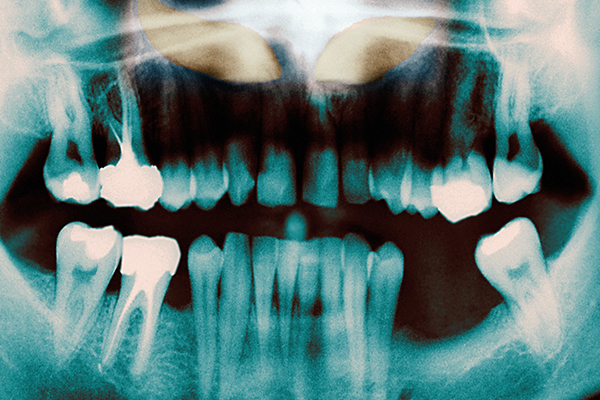

상악동이랑 위 턱뼈 어금니 쪽에 위치해 있는 빈 공간을 말합니다.

상악동이 치아 상실로 인해 밑으로 쳐져 주저 앉으면서 위 턱의 잇몸 뼈가 얇아지게 되는데, 이때 얇아진 잇몸 뼈에는 임플란트 시술을 할 수 없기 때문에 상악동을 들어 올려 확보된 공간에 부족한 뼈를 이식하는 시술입니다.

뼈 확장술이라고도 불리는 릿지 스플릿은 치아가 있는 잇몸 부위와 비교했을 때 잇몸의 폭이 좁아져 안정적으로 임플란트를 식립할 수 없는 상태에서 진행되는 시술입니다.

잇몸 뼈를 쪼갠 후 공간을 넓혀서 스스로 뼈가 증식하도록 만들어 공간을 메꾸어 주는 높은 난이도를 요구하는 고난이도 수술 방법입니다.